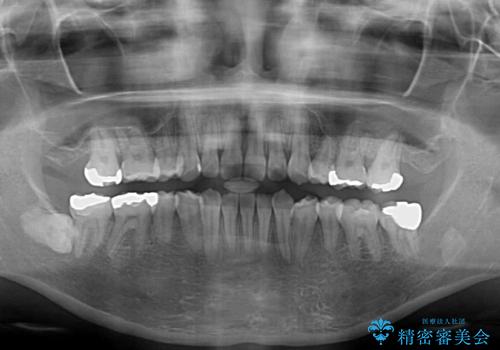

- 左上の八重歯と前歯のデコボコを気にして来院された患者様です。

下顎が左側にズレており、下顎前歯は1歯欠損していたため、左上小臼歯1本を抜歯し、ワイヤー装置にて矯正治療を行うこととしました。

骨格のズレと歯の欠損があったため、仕上がりの調整に時間がかかると思いましたが、舌突出癖の改善や顎間ゴムの装着をしっかりと行ってくださったので、速やかに治療を終えることができました。